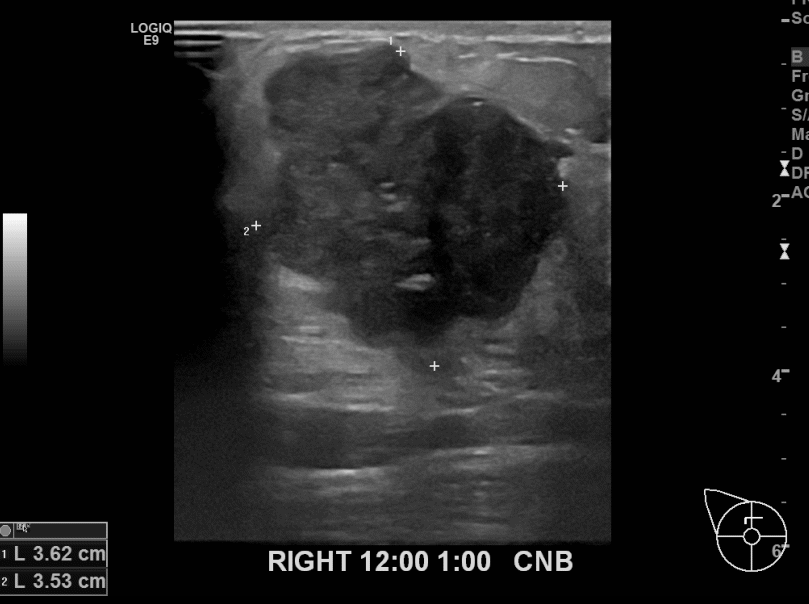

상기환자 우측유방에 만져지는 혹 있어 내원하신 60대여성분으로

악성의심되는 혹 조직검사후 유방암진단되었습니다.